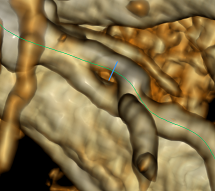

На рисунке ниже изображена трехмерная реконструкция сердца, полученная в результате работы современного томографа:

Для масштаба указана толщина луковицы аорты — 3.2 см, подумать только! Однако, когда у людей возникают проблемы с сердцем из-за сосудов, то речь, как правило, идет вовсе не о таких больших. На изображении видно, что сердце окружено более мелкими сосудами, и некоторые из них ответвляются прямо из крупных артерий. Это так называемые коронарные артерии, которые питают кровью непосредственно сердце. Если в них происходит сужение просвета (стеноз), например, из-за образования кальция, то уменьшается поток крови. Когда стеноз ярко выражен, то случается некроз ткани, другими словами инфаркт. Далее я расскажу о нашем подходе к вычислению границ сосудов, который в результате позволяет автоматически находить сужения и давать им оценку.

Площадь внутренней границы на срезе будет характеризовать тот самый просвет, который нас в итоге интересует. Дальнейшее использование этих данных я считаю тривиальным и не нуждающимся в рассмотрении. Напоследок оставлю изображение экспортированной внутренней границы в 3D: